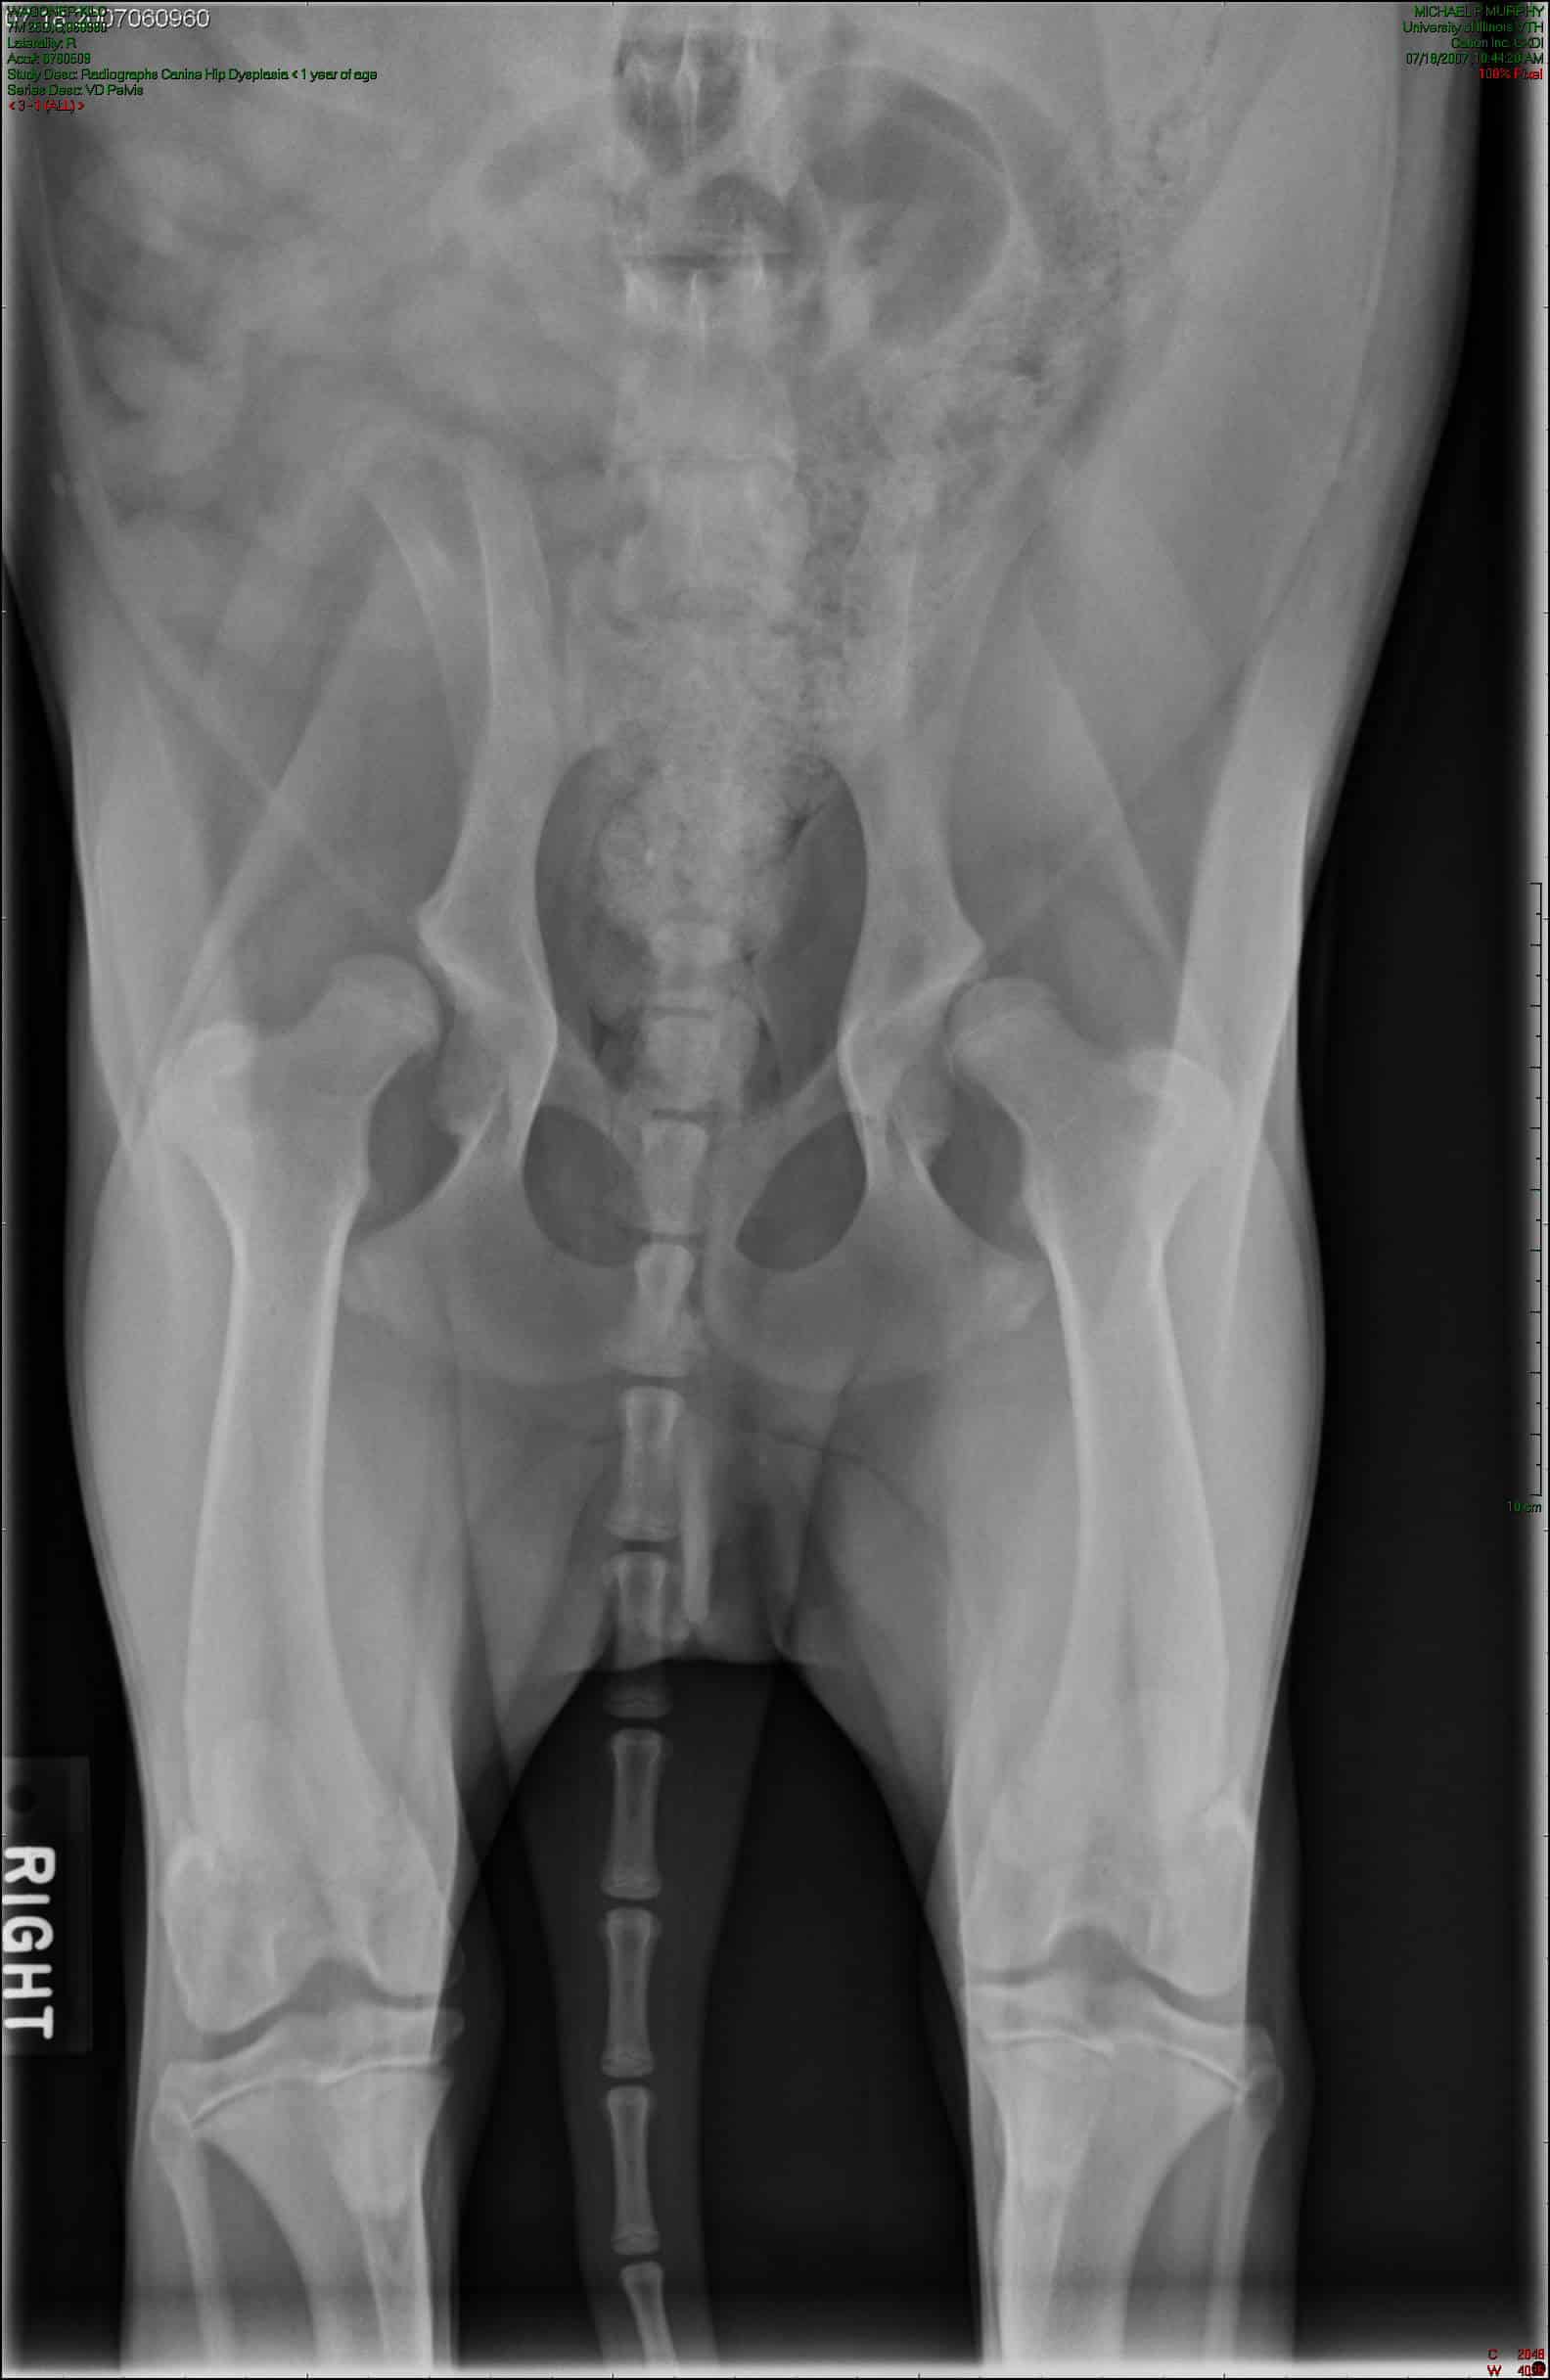

Dysplasie de la hanche chez le chien